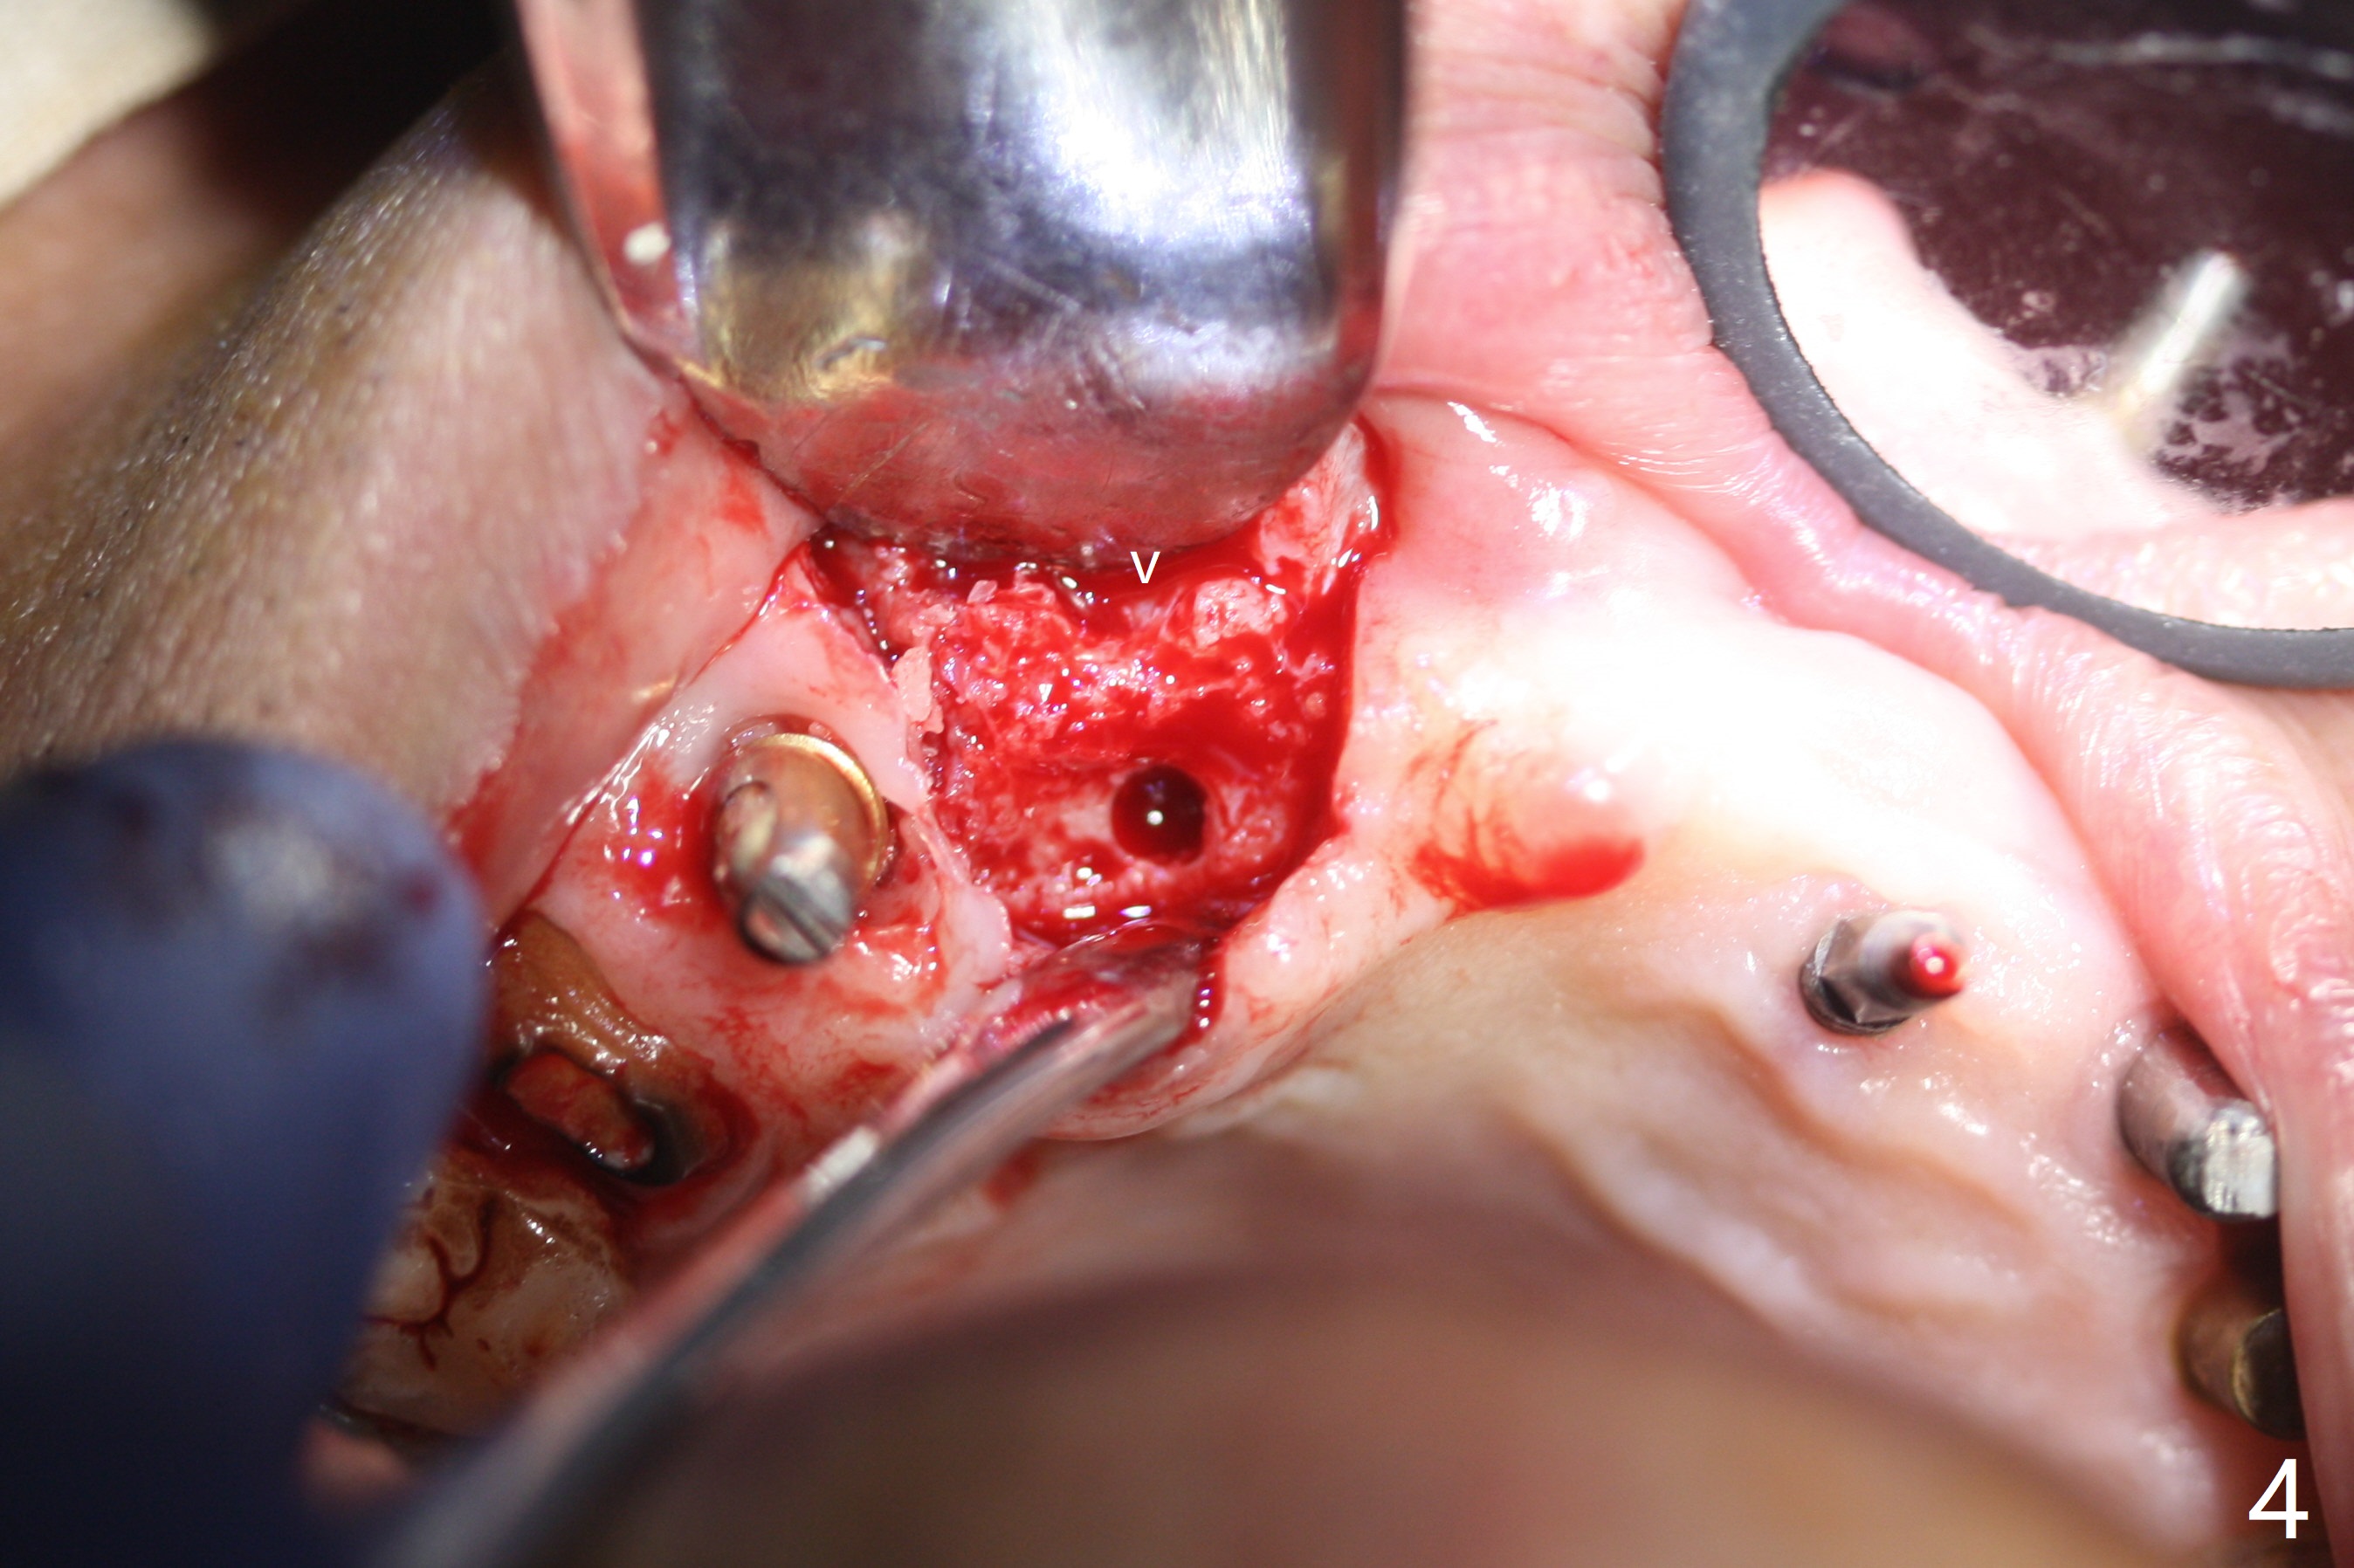

To have enough clearance for the splinted provisional at #6-12 (Fig.1 *), composite has been placed in the posterior teeth (bilateral, *, Fig.2). When the composite is removed, there is no clearance between the implants/abutments of #7 or 10 (Fig.3). Incision is made with removal of the 1-piece implant at #7; there is enough bone to move the osteotomy buccal (Fig.4 arrowhead). When the same implant is placed buccal (Fig.5), there is sufficient clearance for restoration (Fig.6 *), while there is still enough buccal bone left (Fig.7). When the patient returns 5.5 (for #7 and 10)/6.5 (#6,11,12) months postop, his chief complaint is tenderness lingual to #11. In fact, the abutment screw is loose at #11, while the implant at #10 has mobility (Fig.8), which is related to loss of the posterior stops (*) due to wear. There is slight bone loss mesial to #10 implant 5.5 months postop (Fig.10, as compared Fig.9). CBCT taken 5.5/6.5 months postop shows no bone loss (Fig.11-15). The 3x14 mm 1-piece implant at #10 is mobile 9 months postop and is removed and replaced by a 3.5x13 mm 2-piece one with slightly buccal osteotomy (Fig.16). PAs are taken prior to impression (Fig.17,18). The abutment at #12 is loose (<). More composite needs to be added to the occlusal surface of the upper posterior teeth. Finally the patient agrees to have crowns for the upper posterior teeth.